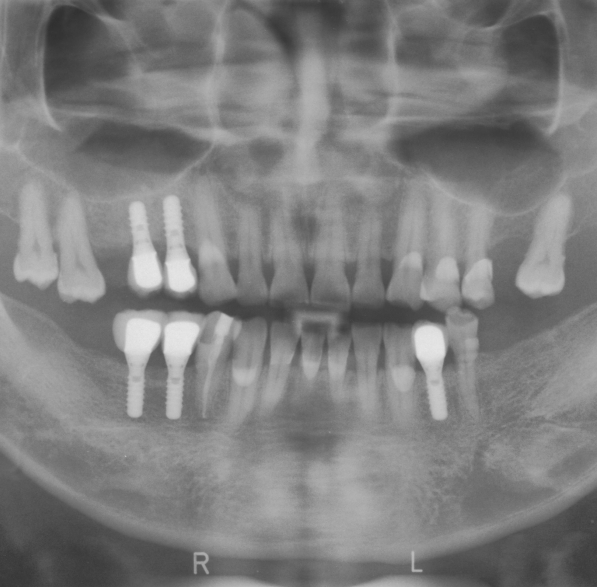

Dental implants are a popular and effective option for people who have lost one or more teeth due to injury, decay, or other causes. A dental implant is a small, sturdy, and biocompatible material that is surgically placed into the jawbone to act as a replacement for the root of a missing tooth.

Dental Implant